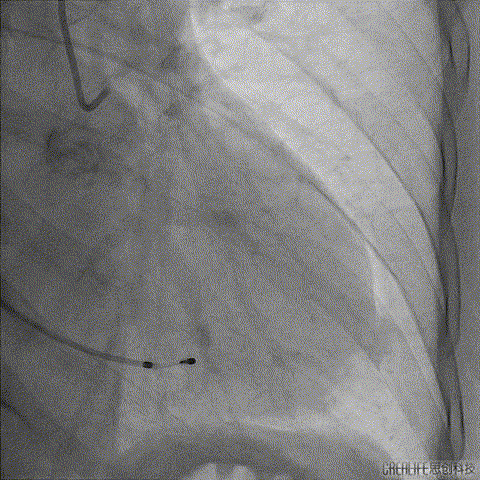

主动脉根部造影前观察确认左右冠脉血流灌注正常;

右冠造影

左冠造影

主动脉根部造影,主动脉瓣重度狭窄并轻度反流,进而导丝跨瓣成功;

主动脉根部造影

导丝跨瓣